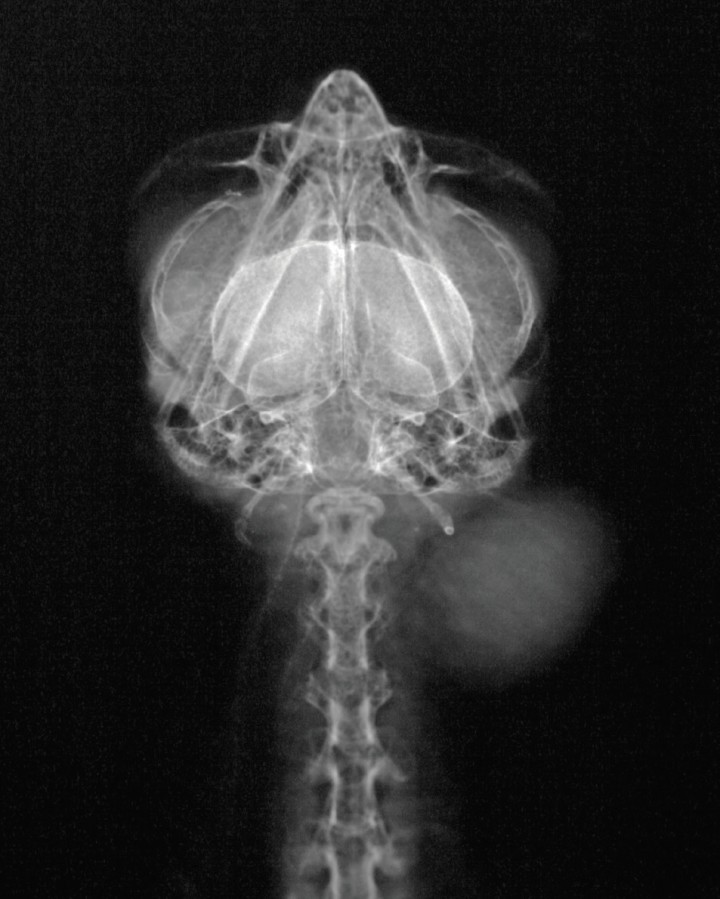

<p>Radiografía DV de la cabeza y cuello. Se aprecia una masa de opacidad tejido blando en la zona izquierda.</p>

Radiografía DV de la cabeza y cuello. Se aprecia una masa de opacidad tejido blando en la zona izquierda.